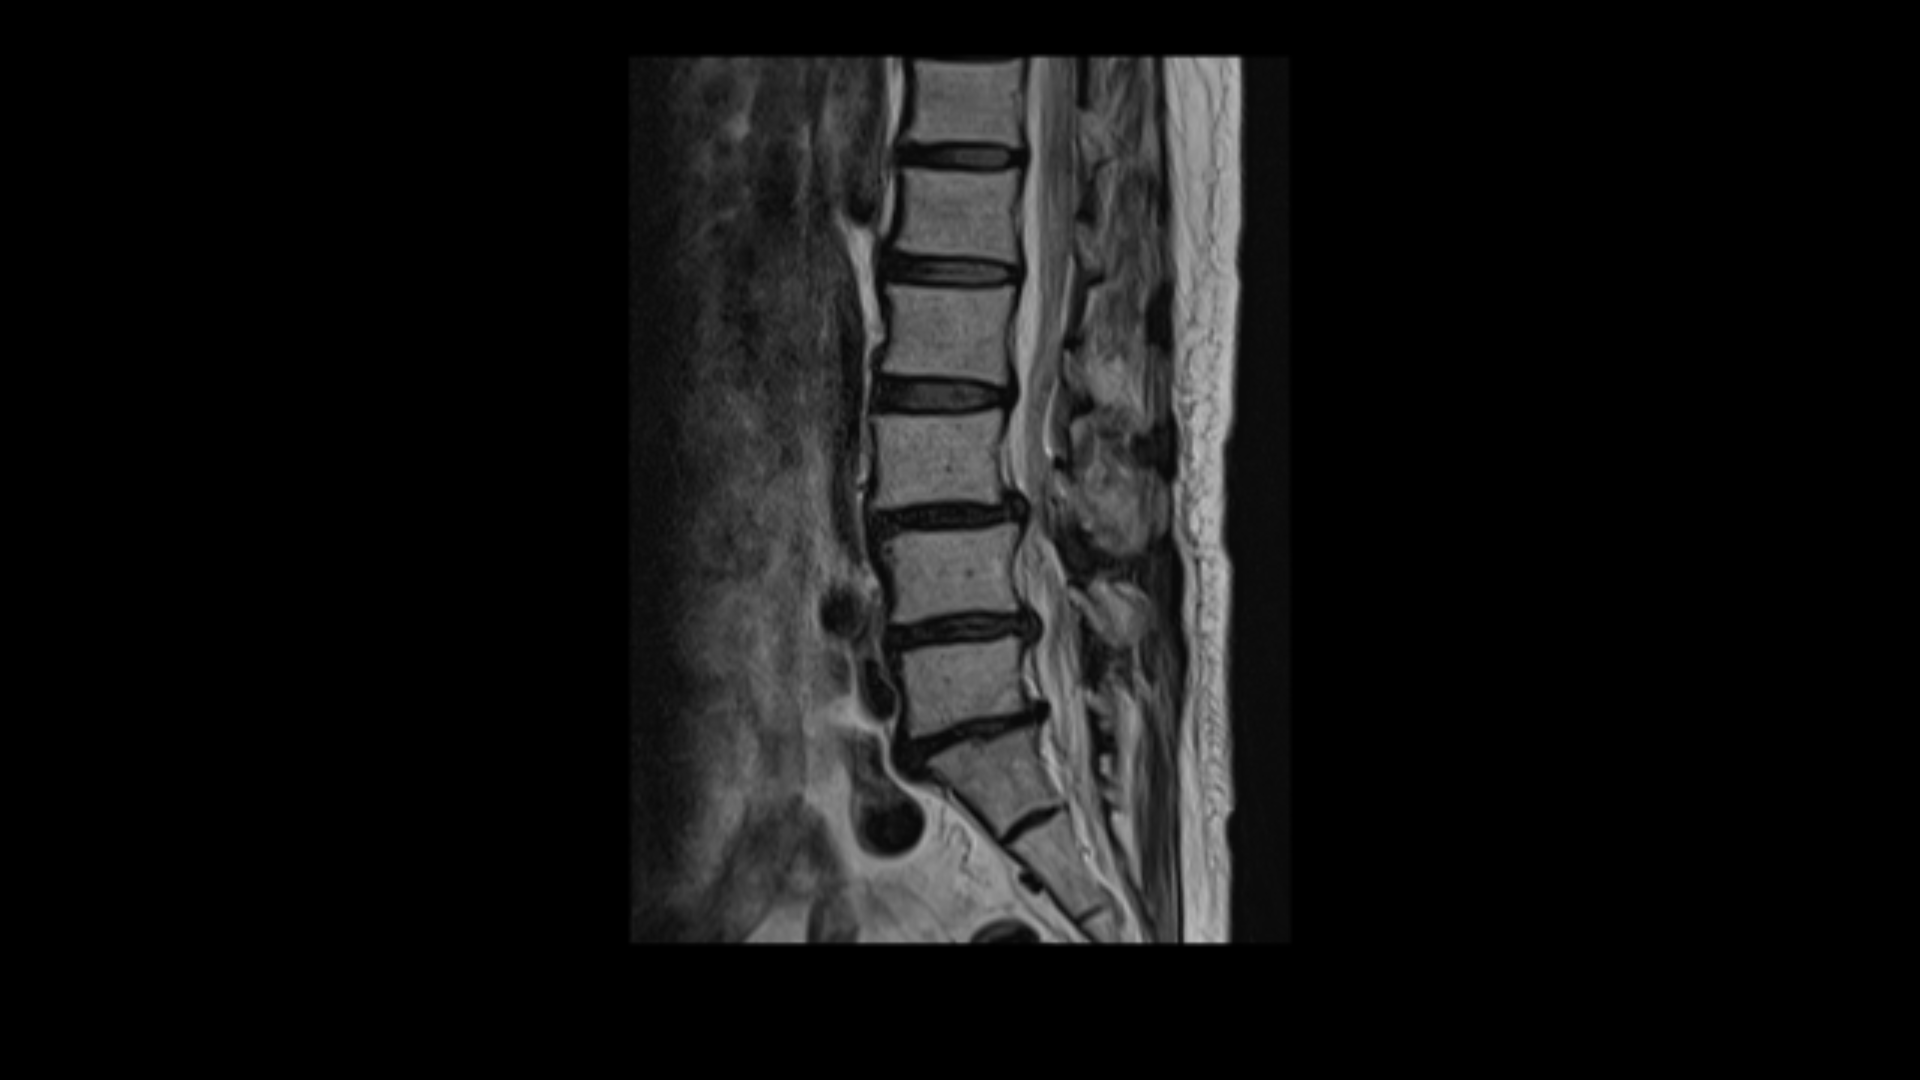

이분 MRI를 보면 3마디에 퇴행성디스크가 밀려 나와 있습니다.

또 3번 4번에는 척추전방전위증이 있습니다.

이 전방전위증 때문에 척추관에 중심성 협착도 있습니다.

4번 5번 디스크가 중앙에서 우측으로 약간 밀려 나와있고

>또 5번 1번에서는 신경이 빠져나가는 오른쪽 추간공이 약간 좁아져 있습니다.

그런데 이분 허리 MRI를 자세히 보면 딱히 신경이 아주 극심하게 눌린 곳도 없습니다.

신경이 조금 눌릴 수는 있어도 심각해 보이지는 않습니다.

신경구멍이 지나가는 길이 여러 가지 퇴행성 변화로 조금씩은 좁아져 있지만 굳이 수술로 특히 여러 마디의 나사를 박는 수술까지 해가며 신경압박을 해소해야 할 정도의 심한 신경눌림은 보이지 않는 겁니다.